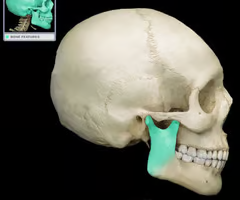

Hyoid bone (only bone that does not articulate directly with any other bone)

Maxilla bone

Mandibular condyle (forms TMJ)

Coronoid process

Mandibular notch

Ramus (“rami” = branches)

Mandibular angle (where ramus and body meet)

Body (forms the chin)